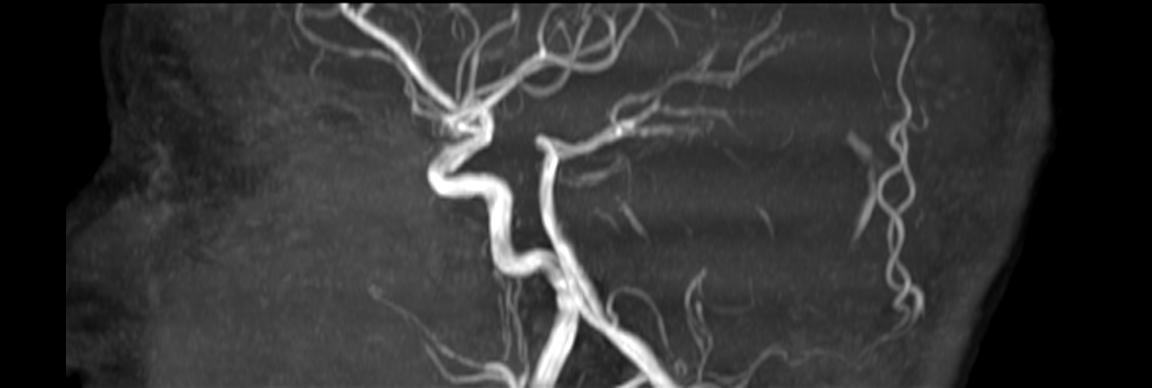

Axial 3D Inflow

Coronal 3D Inflow

Sagittal 3D Inflow